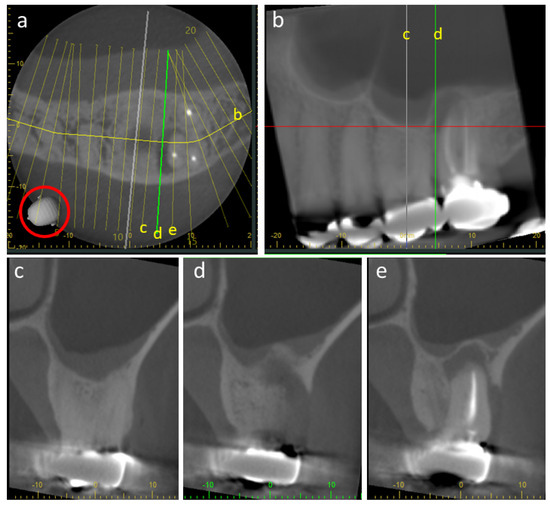

4.2. Metal Artifacts and Use of Metal Artifact Reduction Software

- MacDonald, D.; Alebrahim, S.; Yen, E.; Aleksejuniene, J. Cone-beam computed tomographic reconstructions in the evaluation of maxillary impacted canines. Imaging Sci. Dent. 2023, 53, 145–151. [Google Scholar] [CrossRef]